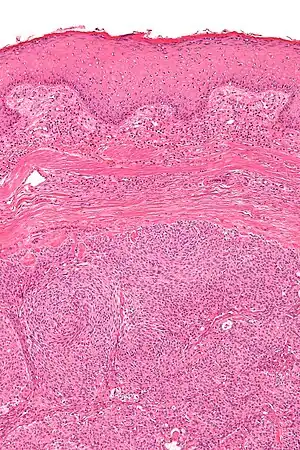

Micrograph showing an acrospiroma. H&E stain.

Hidradenoma refers to a benign adnexal tumor of the apical sweat gland.[1][2] These are 1–3 cm translucent blue cystic nodules. It usually presents as a single, small skin-colored lesion, and may be considered closely related to or a variant of poromas.[3] Hidradenomas are often sub-classified based on subtle histologic differences, for example:[4]

Discussion of sweat gland tumors can be difficult and confusing due to the complex classification and redundant terminology used to describe the same tumors. For example, acrospiroma and hidradenoma are synonymous, and sometimes the term acrospiroma is used to generally describe benign sweat gland tumors. In addition, a single lesion may contain a mixture of cell-types.[2] There has also been a change in understanding about how tumors that were previously believed to strictly derive from specific sweat gland types may, in fact, derive from both eccrine or apocrine glands.[5][6]